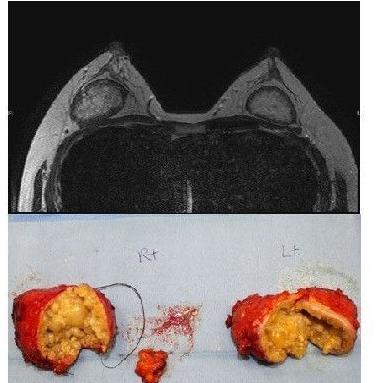

通过上图X光片可以看到肿块和坏死的脂肪。从取出的囊肿可以看出,外表并没有包膜,里面是黄色的粘稠液体。进行组织检查后发现是脂肪坏死,营养不良钙化。